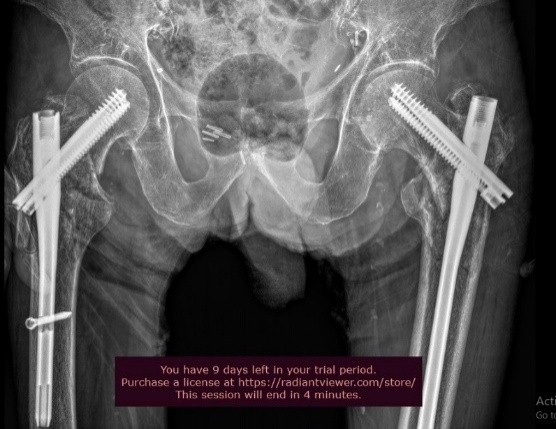

An 85-year-old male patient who was hit by a car as a pedestrian presented at our emergency department. The patient has a medical history of chronic obstructive pulmonary disease and compensated chronic cardiomyopathy. He lives with his son and could independently perform daily activities. On examination, external rotation and shortened lower limbs on both sides were evident, as well as pain in palpation and/or mobilization of the lower extremities bilaterally. Following the radiological study, a transtrochanteric fracture of the right femur and a subtrochanteric fracture of the left femur were revealed (Fig. 1).

Figure 1: Anteroposterior view of the pelvis. Right intertrochanteric fracture. Left subtrochanteric fracture.